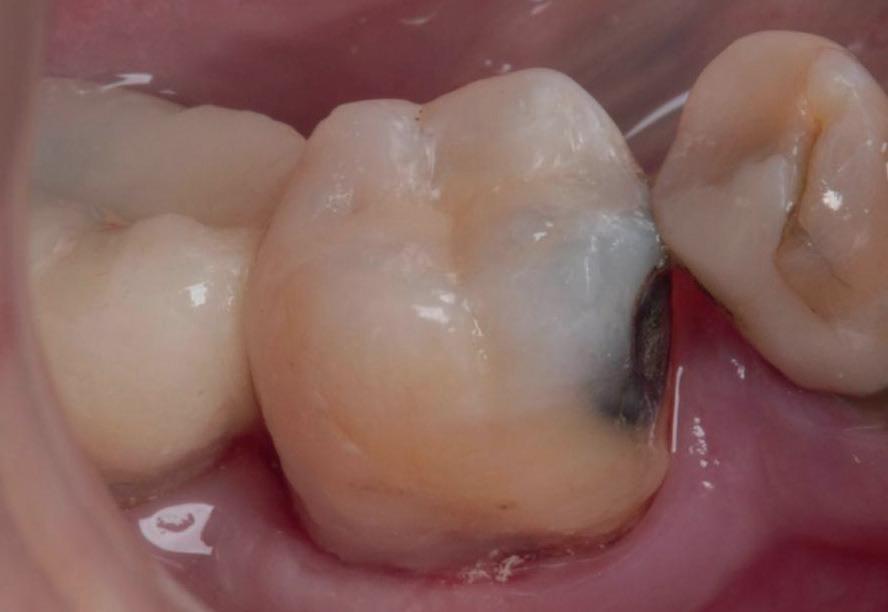

PREZENTARE DE CAZ

Un pacient caucazian în vârstă de 77 ani s-a prezentat la clinica autorului după cinci ani în care nu a fost la niciun control stomatologic. Examinarea clinică a arătat o pierdere semnificativă de os, parodontită cronică și multiple edentații care au destabilizat ocluzia. Pacientul a raportat sensibilitate la rece la nivelul primului molar drept inferior nr. 46, în special la ingerarea de lichide reci. Radiografia periapicală a confirmat constatările examenului clinic; în

plus, s-a detectat și prezența unei carii radiculare la nivelul rădăcinii distale a aceluiași molar, cu răspuns pozitiv la testul de sensibilitate (fig. 1-2).

Planul de tratament a început cu accent pe restabilirea sănătății parodontale. Într-o ședință ulterioară, odată cu îmbunătățirea stării parodonțiului, s-a efectuat restaurarea molarului nr. 46. Sub anestezie la Spina Spix pe partea dreaptă și

Figurile:

1. Situația clinică inițială.

2. Radiografia inițială.